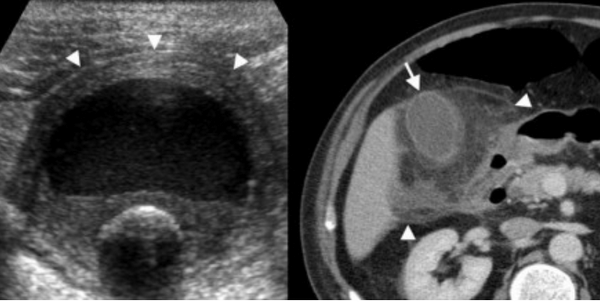

Слева — УЗИ — желчного пузыря у 59 летней женщины с острым холециститом. Субсерозный отек так, как гипоэхогенное утолщение между гиперэхогенными слоями (мышечным и слизистым). Справа — КТ брюшной полости с контрастным усилением. Также визуализируется субсерозный отек так, как наружный слой гиподенсный.

Острый калькулезный холецистит. После контрастного усиления визуализируется растянутый желчный пузырь (белые наконечники) со слегка утолщенной стенкой. Визуализируется камень в шейки желчного пузыря (белая стрелка).

УЗИ и КТ желчного пузыря. Ксантогранулематозный холецистит. Слева на УЗИ визуализируется (помечено стрелками) утолщение стенки желчного пузыря с интрамуральным включением и с камнем в просвете органа. Справа на КТ выявляется утолщение стенки с гиподенсными включениями.

УЗИ (слева) и КТ (справа) желчного пузыря. На УЗИ ярко выраженное утолщение стенки желчного пузыря (указаны белыми стрелками). Множественные камни в просвете желчного пузыря (указано стрелкой). Компьютерная томография с контрастным усилением. На КТ визуализируются утолщение стенки с внутристеночными гиподенсными включениями. На КТ также выявлено, что процесс распространился на печень (указано стрелкой).